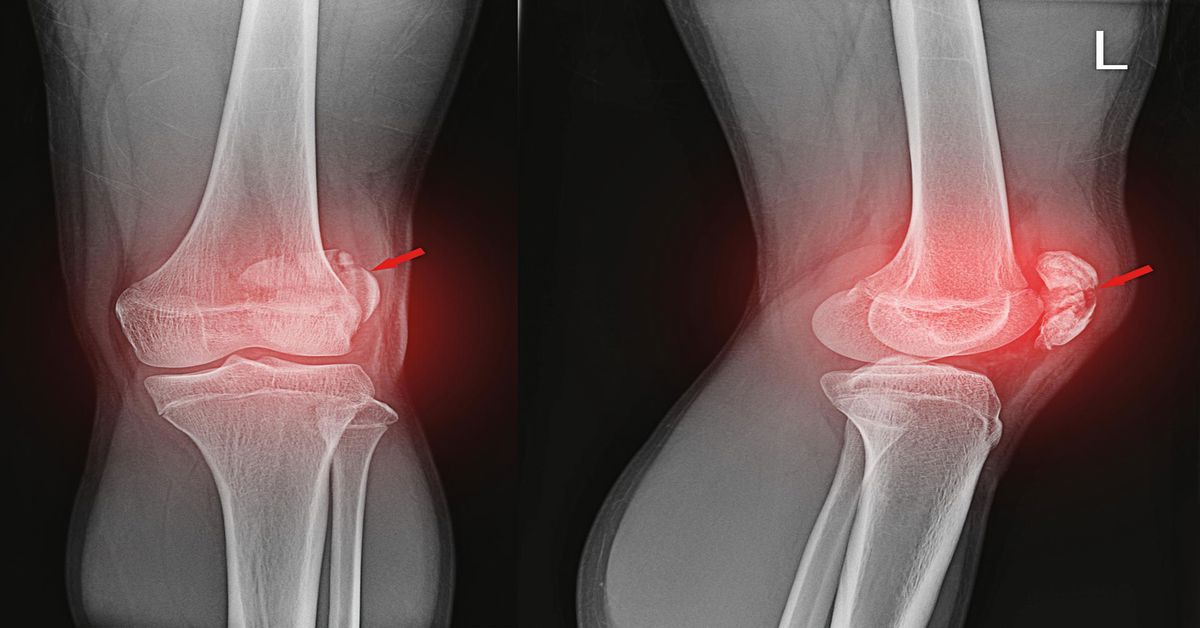

Hastanın durumuna göre uygulanacak tedavi yöntemi belirlenir. Hafif vakalarda eklem, uzman hekim tarafından yerine oturtulur. Bu işleme kapalı redüksiyon denir. Bu işlem, ağrının azalması ve eklemin eski işlevine kavuşması için genellikle ağrı kesici veya anestezi altında yapılır. Daha ileri vakalarda bağ, kas veya kemik dokularında hasar meydana gelebilir. Bu durumlarda cerrahi müdahale gerekebilir.

Hafif vakalarda cerrahi dışı tedavi yöntemleri tercih edilir. Bu durumda eklem, uzman hekim tarafından yerine oturtulur. Bu işleme kapalı redüksiyon denir ve genellikle ağrı kesici veya anestezi altında yapılır. Sonrasında eklemin sabit kalması için atel, bandaj veya alçı uygulanır. Dinlenme sürecinde ekleme aşırı yük bindirilmemesi ve bölgenin korunması gerekir.

İleri vakalarda cerrahi müdahale gerekebilir. Bağ, kas veya kemik dokularında yırtık ya da kırık tespit edilirse ameliyat yapılır. Eklem çıkığı tedavisi, cerrahi aşamada eklem yapılarının onarılmasını ve doğru hizalanmanın sağlanmasını içerir. Ameliyat sonrası dönemde fizik tedavi, eklem hareketliliğini geri kazandırmak için büyük önem taşır.